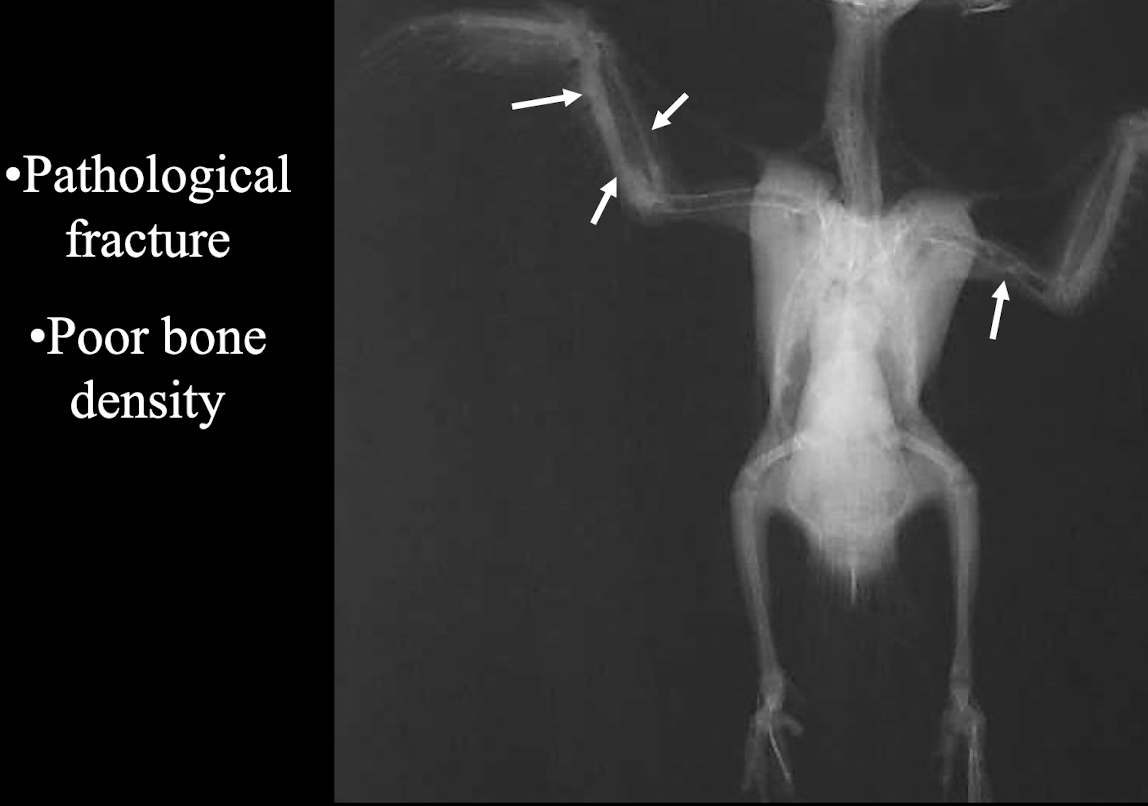

What radiographic signs are indicative of Metabolic Bone Disease in birds?

Pathological fracture and poor bone density.